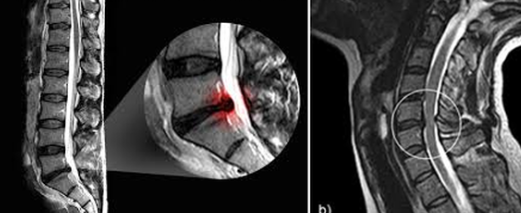

목디스크의 진단은 일반적으로 여러 가지 영상 촬영 기술을 통해 이루어집니다. 단순 방사선 검사를 통해 경추부의 전반적인 구조를 확인할 수 있으며, 더 구체적인 진단을 위해서는 자기공명영상(MRI)을 활용하여 디스크의 상태와 신경 압박 정도를 파악할 수 있습니다. 또한 컴퓨터 단층촬영(CT)을 통해 디스크의 경화 상태와 척추 뼈 구조를 정밀하게 살펴볼 수 있습니다.